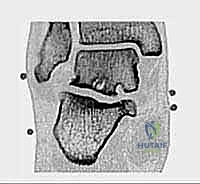

1. متلازمة انحشار الكاحل الخلفي والعظم الزائد (Os Trigonum Syndrome)

تُعد هذه المتلازمة من أكثر الأسباب شيوعاً، خاصة لدى الرياضيين (لاعبي كرة القدم) والراقصين (الباليه). العظم الزائد (Os Trigonum) هو عظم إضافي خلقي صغير يقع خلف عظم الكاحل (Talus). في الحالات الطبيعية، قد لا يسبب ألماً، ولكن مع الثني القسري المتكرر للقدم نحو الأسفل (Plantar Flexion)، ينحشر هذا العظم بين عظم الظنبوب وعظم العقب، مما يؤدي إلى التهاب شديد وتمزق في الأنسجة المحيطة به.

* الأشعة السينية (X-rays): بوضعيات خاصة (Lateral view) لرؤية العظم الزائد (Os Trigonum) والنتوءات العظمية وتضيق المسافات المفصلية.

* الأشعة المقطعية (CT Scan): تُستخدم في حالات معينة لعمل خريطة ثلاثية الأبعاد للكسور القديمة أو التكلسات العظمية المعقدة قبل الجراحة.